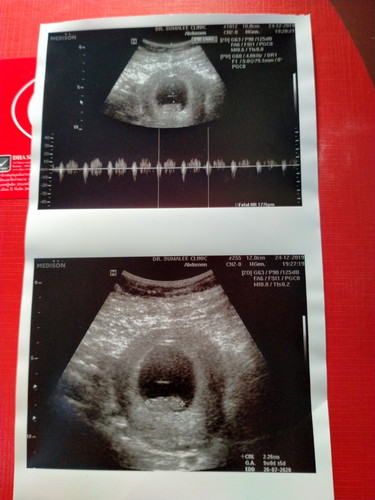

แบบนี้กำหนดคลอด28/07/63ใช่ไหมคะ.....แต่ตอนนี้อายุครรภ์ได้12w2dแล้วคะ..

ควรเอ่อายุครรภ์ตามอัลตร้าซาวครั้งแรกนะคะ ในอัลตร้าซาวบอกว่า 9w+0คะ

แต่ตอนนี้เราอายุภ์12w3dค่ะ

ของเรา11weekทำไมมองอะไรไม่เห็นเลยนอกจากกลมๆ

ประมาณนี้เหมือนกันจ้า อีกสอง-สามสัปดาห์จะเห็นแขนขาชัดเจนขึ้นค่ะ บางทีก็ขึ้นอยู่กับประสิทธิภาพ(รุ่น-ยี่ห้อ) ของเครื่องอัลตร้าซาวน์ด้วยค่ะ